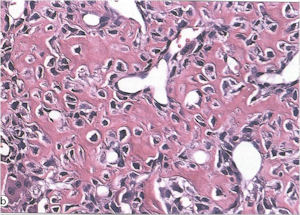

Microscopic Pathology

- Interlacing network of bone trabeculae in a loose fibrovascular stroma

- Prominent vessels

- Osteoblasts are plump, active, scattered mitotic figures

- Osteoblasts line up around periphery of trabeculae (Osteoblastic Rimming)

- Soft tissue component usually surrounded by shell of reactive bone or periosteum (Egg Shell Rim of Calcification)

- No cartilage production (as opposed to osteosarcomas that may contain areas of cartilage)